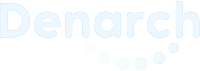

Before

Emily Ward came to our clinic with long-standing dental issues that were beginning to significantly affect her daily life. She had lost several posterior (back) teeth, which created an imbalance in her bite. Over time, this caused her bite to deepen abnormally, leading to excessive pressure on her front teeth.

As a result, Emily experienced:

Difficulty chewing

A collapsed bite that altered her smile

Mobility of her remaining anterior teeth

Early signs of functional and aesthetic deterioration